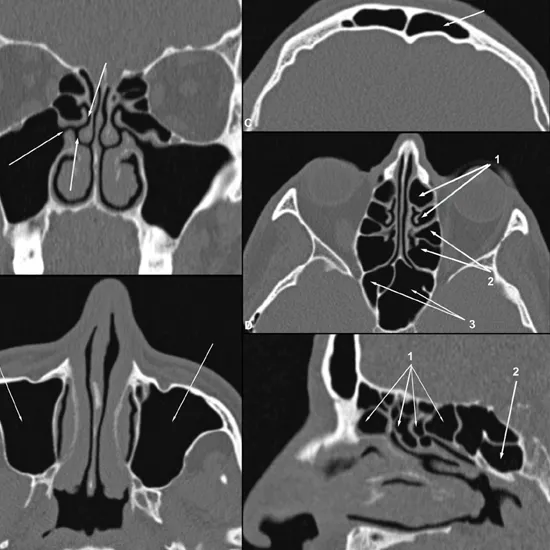

HRCT PNS Axial is a high resolution computed tomography paranasal sinus axial view. This imaging scan is used to obtain a high-resolution image of sinus cavities from top to bottom. This helps diagnose and evaluate suspected sinus diseases.

Why is HRCT PNS Axial Done?

1. To diagnose the severe sinusitis

2. To diagnose the abnormal growth and its size in the nasal cavity.

3. To determine the infections of sinusitis

4. To detect the existence of fluid in sinus cavities.

5. To detect the injury in the sinus cavities

6. To detect the polyps in sinus cavities

7. To detect the birth defects related to sinus.